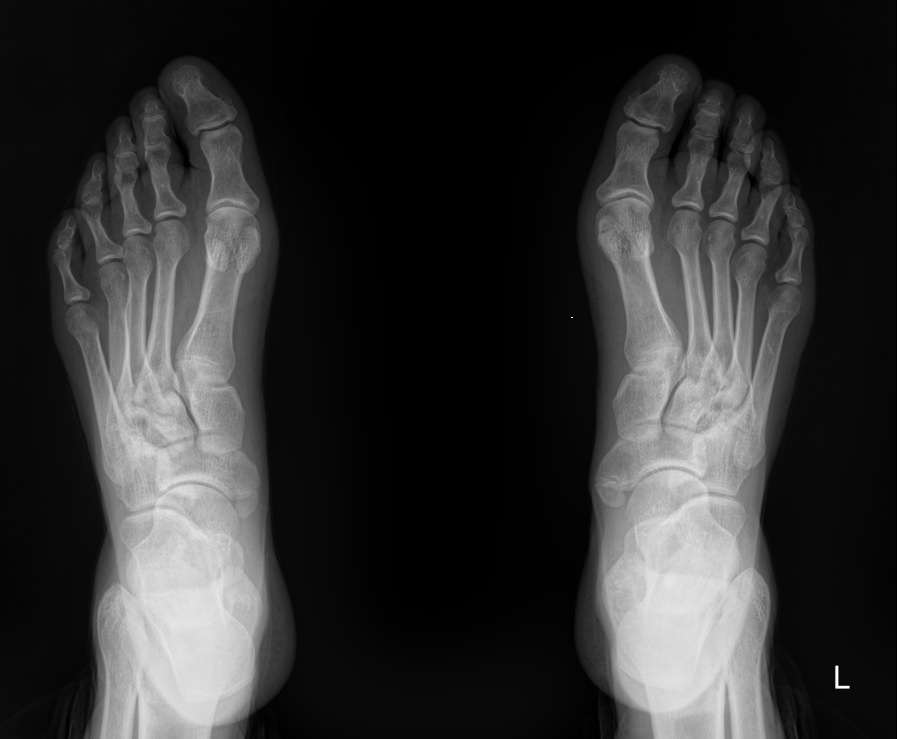

На снимке обеих стоп можно будет сравнить изменения, произошедшие в каждой стопе:

• В состоянии суставных щелей и соответствии суставных поверхностей друг другу;

• В состоянии костной ткани и надкостницы и их целостности;

• В мягких тканях.

Также указываются обнаруженные новообразования, их местоположение.